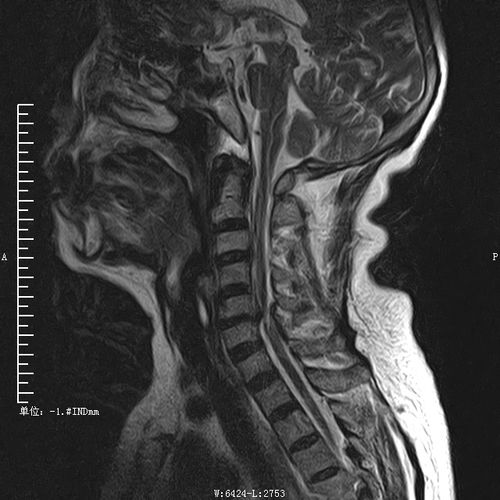

正常颈椎核磁图片解读

正常颈椎核磁图片解读,颈椎病mri图片讲解

正常颈椎影像解剖图

术前颈椎核磁共振检查显示颈脊髓于4/5,6/7平面损伤

术后复查核磁可见: 颈椎4,5节段压迫完全解除,神经恢复正常形态.